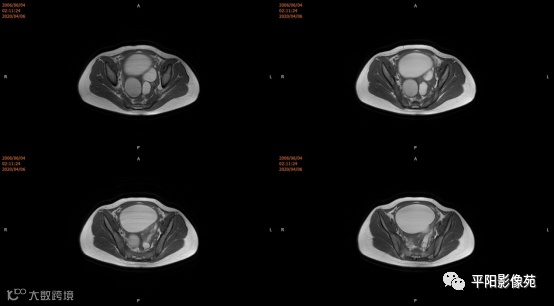

子宫10cm×12cm大小,饱满,呈紫红色,子宫下段增粗膨大呈柱状,右侧卵巢可见一约18*15cm大小的肿物,表面呈紫红色,输卵管明显增粗膨大,伞端及卵巢粘连包裹于子宫后壁及侧盆壁,左侧卵巢可见一约8*7cm大小的囊肿,左侧输卵管增粗膨大伞端包裹粘连于子宫后壁及侧盆壁,直肠粘膜粘连于子宫后壁。部分大网膜粘连于子宫及卵巢表面。 注射器针头刺入子宫肌层至宫腔,抽取出大量暗红色血液,宫腔内积血,子宫缩小,子宫下段膨大,不排除生殖道畸形,双侧卵巢巧克力囊肿可能,钝性分离粘连,针头刺入右侧卵巢囊腔,吸出咖色液体约800ml,娩出右侧卵巢,切开右侧卵巢囊肿表面组织达囊壁,钝性剥离囊肿,剥离过程中可见大量黑褐色液体流出,3-0可吸收线缝合囊腔止血使卵巢成形,大小约5*6cm,同法处理左侧,使左卵巢成形,分离双侧输卵管粘连,暴露伞端,行宫腔穿刺可抽取出大量暗红色血液,考虑生殖道畸形,需改阴式手术探查,破坏处女膜,术中向患者家属交待病情,需改阴式手术破坏处女膜,患者家属表示理解,同意改阴式探查并签字。 患者取膀胱截石位,常规消毒铺巾,见外阴外观发育正常,分开小阴唇,见尿道口下方可见处女膜环,剪开处女膜环,可见阴道壁约1cm,前为盲端,分开处女膜后,于尿道下方阴道口位置,将1:10000的肾上腺素注入阴道直肠间隙,在尿道口下方阴道壁痕迹处横切约2.5cm,钝性分离,可及一囊肿,表面淡紫色,20ml注射器经此处穿刺,抽出暗褐色积血,用注射器向阴道积血方向穿刺,抽出褐色积血,探查囊腔与宫腔相通,未见明显宫颈组织,上段未见阴道粘膜,考虑宫颈缺如及生殖道畸形,清理宫腔积血,将子宫下段最低端缝合于约1cm的阴道粘膜上,形成宫颈形状,宫腔放置一根引流管,查无出血。

(左卵巢)子宫内膜异位囊肿,伴囊状滤泡形成,(右卵巢)纤维囊壁组织,未见上皮细胞被覆,符合单纯囊肿。

宫颈缺如、阴道闭锁

4.MRI检查 对软组织分辨率好,能够清晰区分子宫及阴道,对子宫内膜、结合带、肌层可清晰分辨;能明确子宫、宫颈、阴道结构异常的部位、范围、性质等。宫腔内经血潴留时,宫腔内见短T1长T2信号。